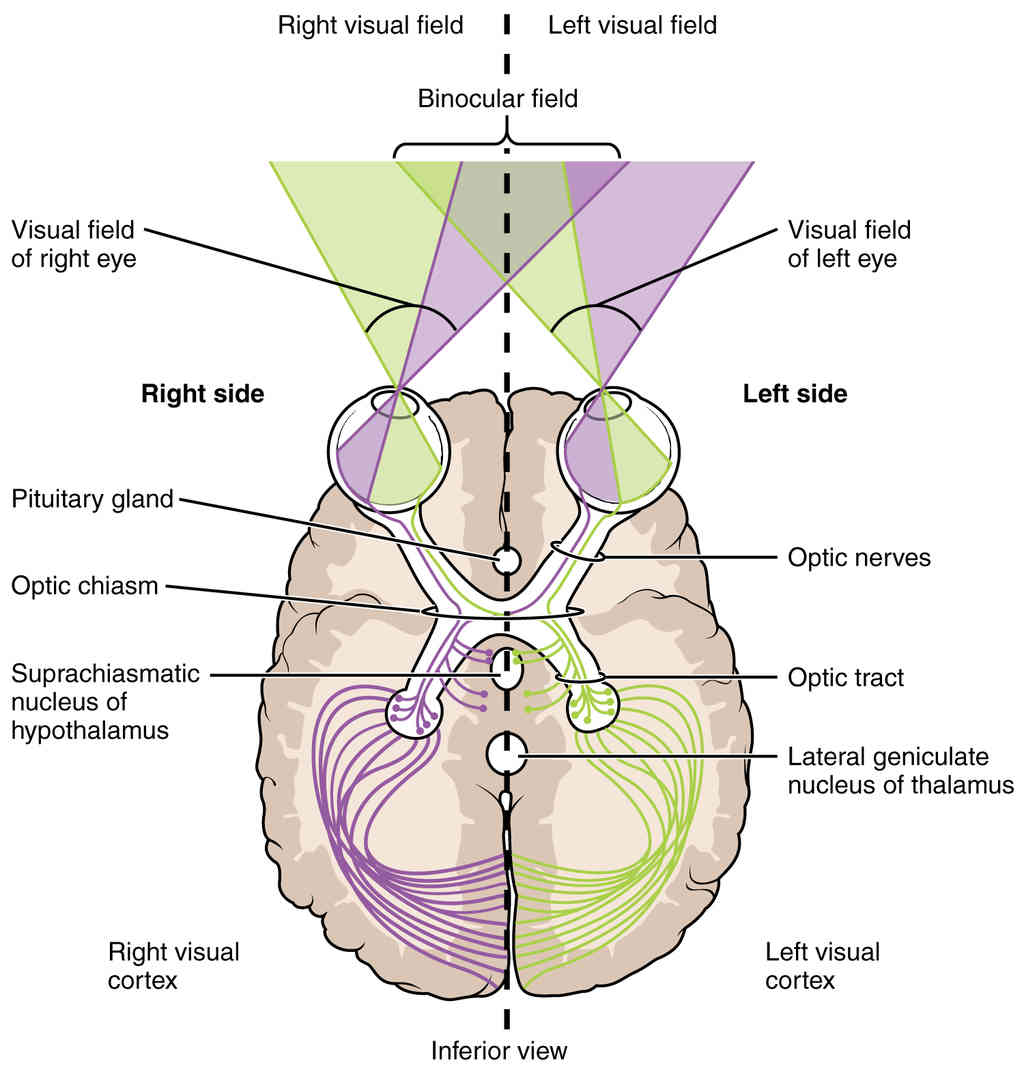

This page is under construction. For now, it is just a resource of the images found in the OpenStax Anatomy and Physiology Handbook. It wil slowly change into a revision tool. Each slide has a number. Use this to refer to the slide. When completed, it will have an unlabelled section, with labelled slides in parallel. On the unlabelled slides, write your answer and use the labelled slide to assess yourself. Keep track by also noting the number on each slide. Improvement at each attempt is important, more so than full marks on a first attempt.